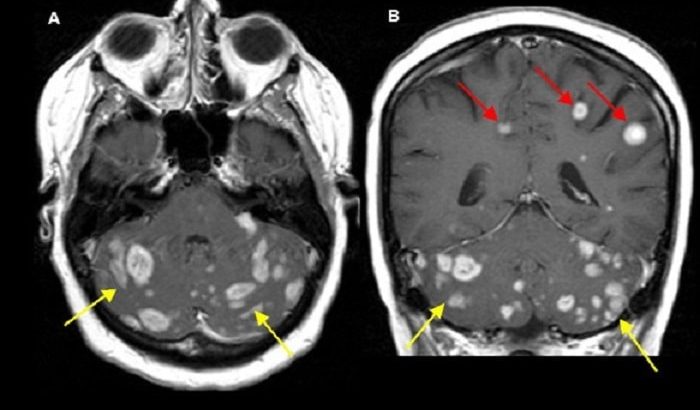

•研究表明,大约80%以上的转移性脑瘤是由脑内多个肿瘤引起的,10-20%是由单个肿瘤引起的。

•大约85%的转移病灶位于大脑,15%位于小脑。

•多发性脑转移很常见。

•两个或更多转移性脑瘤是常见的。